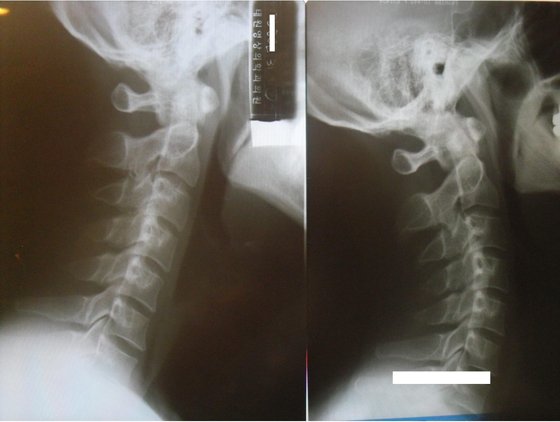

왼쪽이 일자목 상태의 경추 X-ray고, 오른쪽이 추나치료 후 정상적으로 치료된 경추 X-ray 사진이다. 오른쪽 사진처럼 앞쪽으로 C 커브를 그려야 정상이다. 이렇게 치료되려면 한의사와 환자 모두 상당한 노력이 필요하다. [사진 박용환] |

추나 치료는 일자목을 치료하는데 일등공신이다. 추나 치료는 비단 뼈를 교정하는 것뿐만 아니라 뼈 주변 근육·근막·인대까지 바로 잡는 근막이완술과 강화기법까지 함께 할 수 있다. 최근 국가에서 의료보험 적용을 지정했기 때문에 예전보다 상당히 싼 수가로 치료받을 수 있게 되었다.